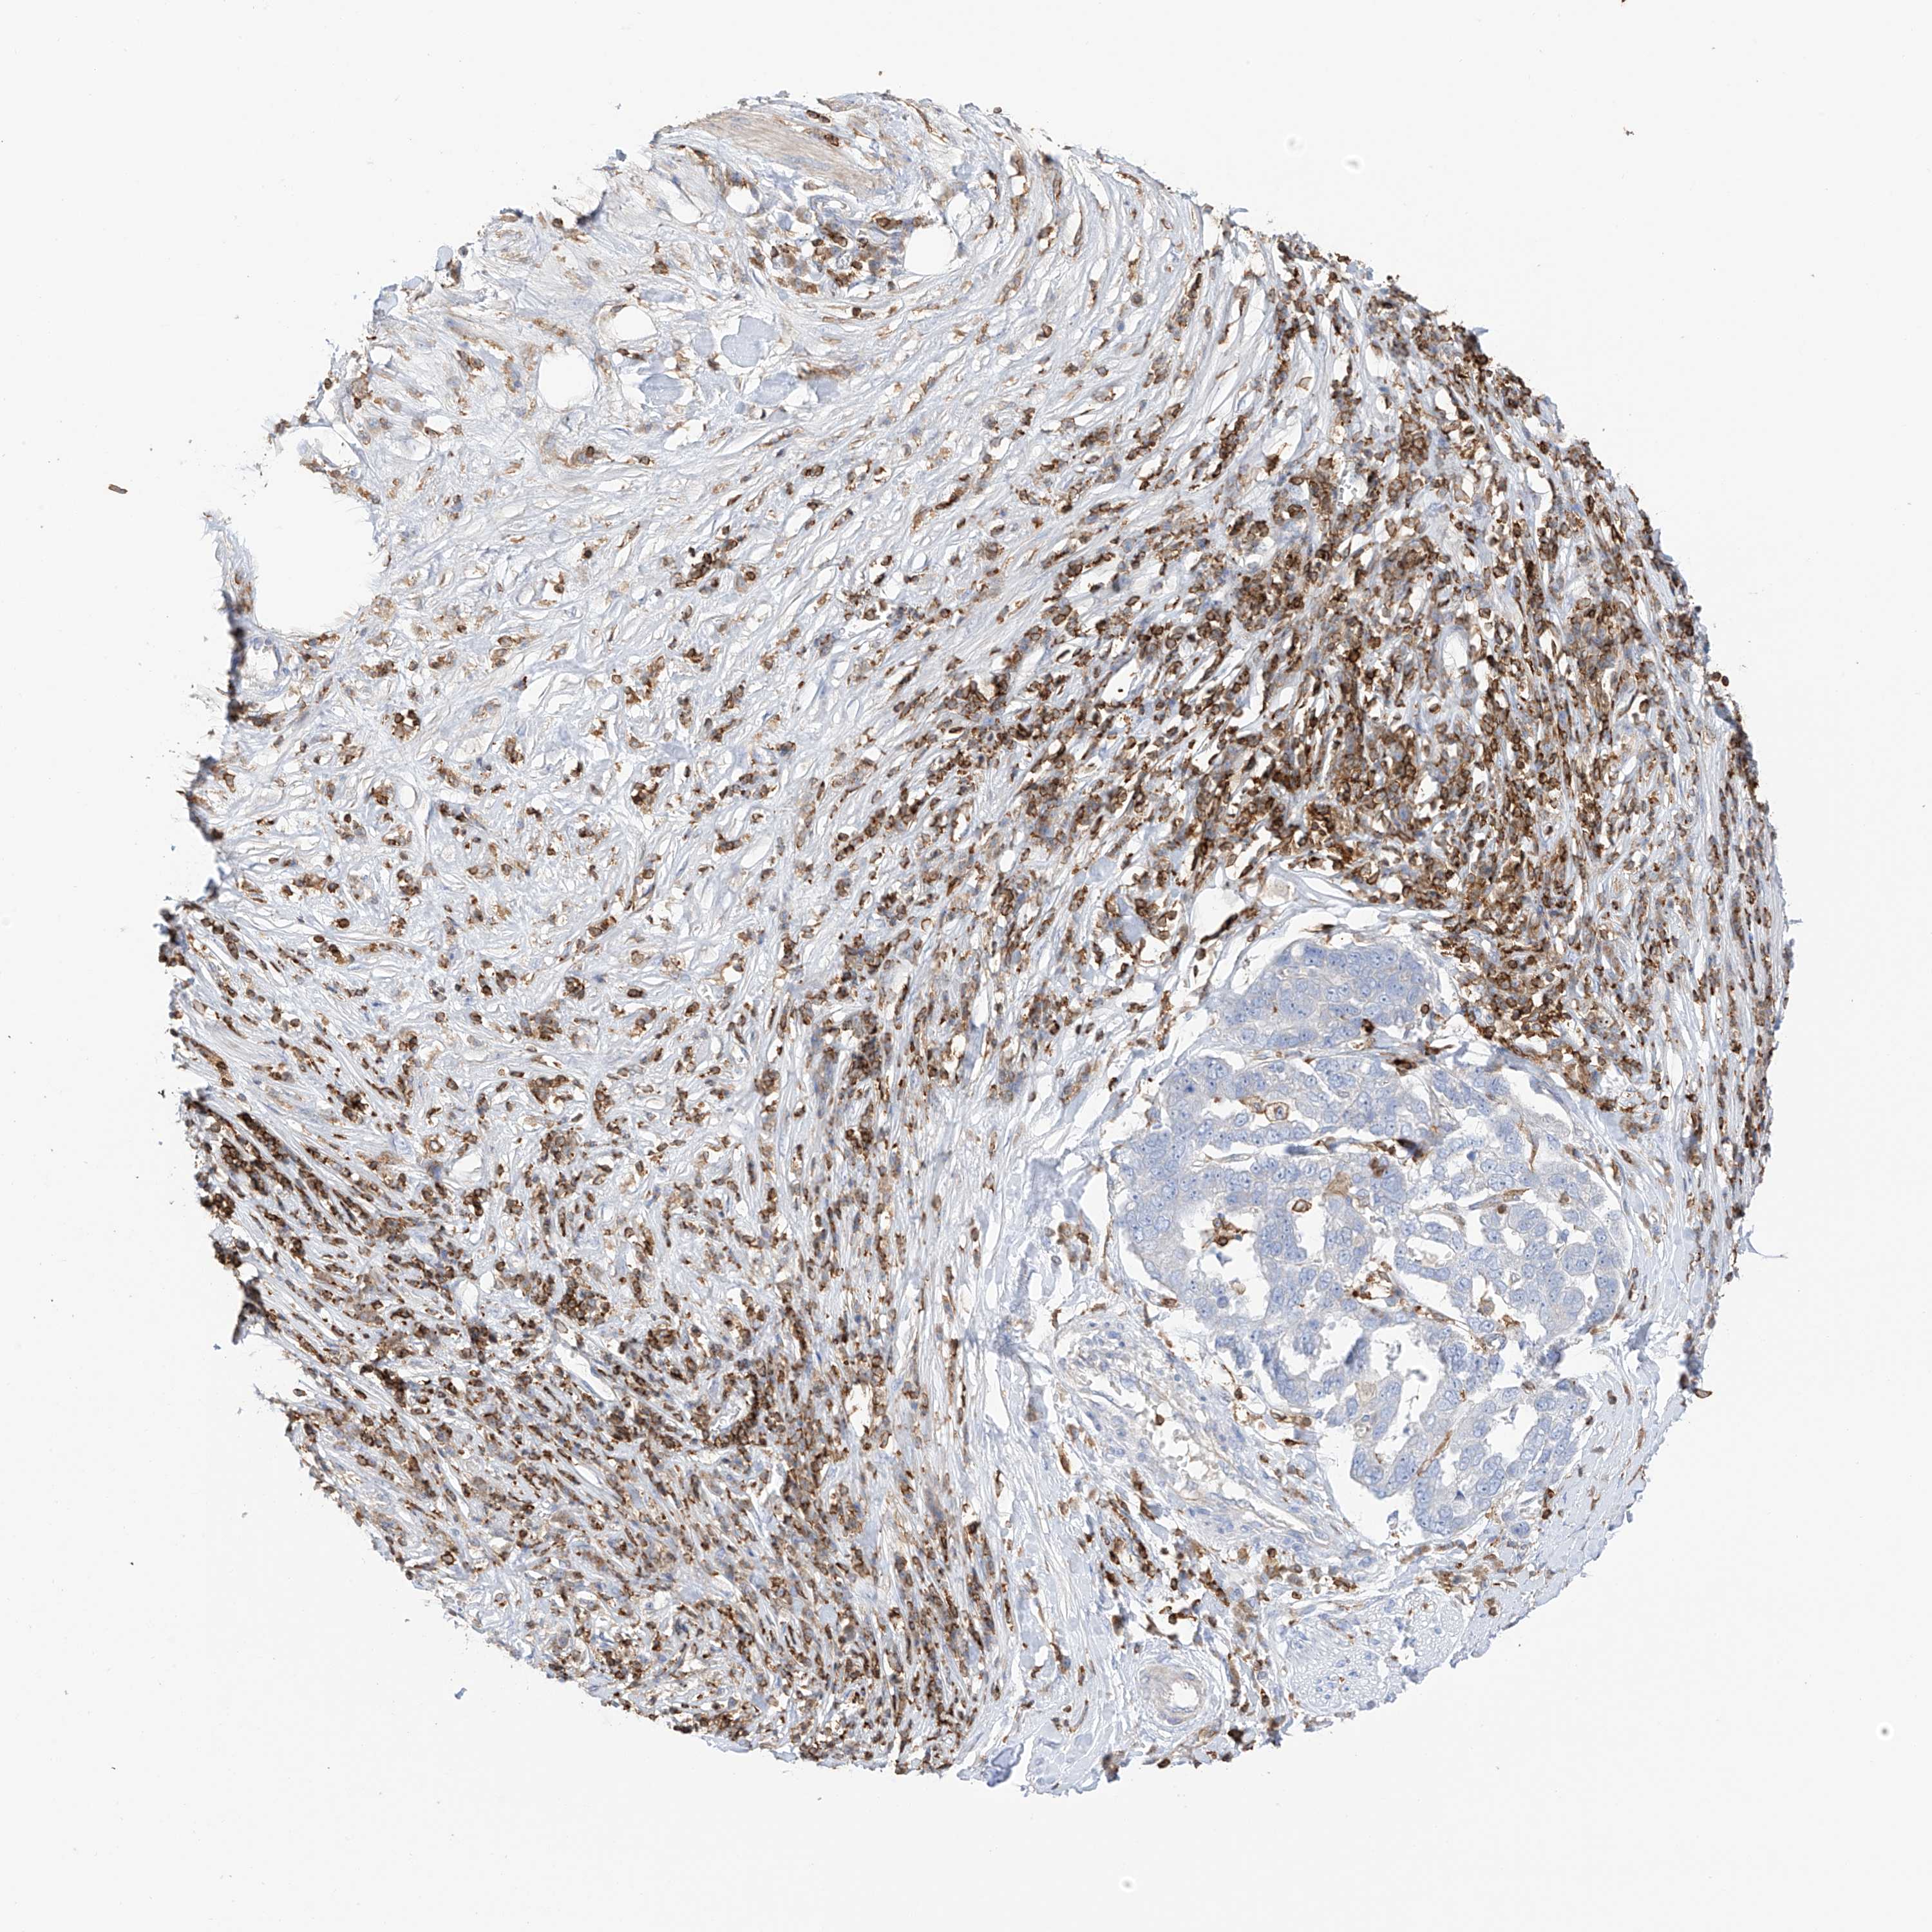

PANCREATIC CANCER - Protein expressioni

A mouse-over function shows sample information and annotation data. Click on an image to view it in a full screen mode. Samples can be filtered based on level of antibody staining by selecting one or several of the following categories: high, medium, low and not detected. The assay and annotation is described here.

Note that samples used for immunohistochemistry by the Human Protein Atlas do not correspond to samples in the TCGA dataset.

Antibody stainingi

Antibody staining in the annotated cell types in the current human tissue is reported as not detected, low, medium, or high, based on conventional immunohistochemistry profiling in selected tissues. This score is based on the combination of the staining intensity and fraction of stained cells.

Each image is clickable and will lead to virtual microscopy that enables deeper exploration of all samples and also displays staining intensity scores, fraction scores and subcellular localization as well as patient and tissue information for each sample.

Antibody HPA035346

Antibody HPA061395

Staining

High

Medium

Low

Not detected

Intensity

Strong

Moderate

Weak

Negative

Quantity

>75%

75%-25%

<25%

None

Location

Nuclear

Cytoplasmic/membranous

Cytoplasmic/membranous,nuclear

Adenocarcinoma, NOS